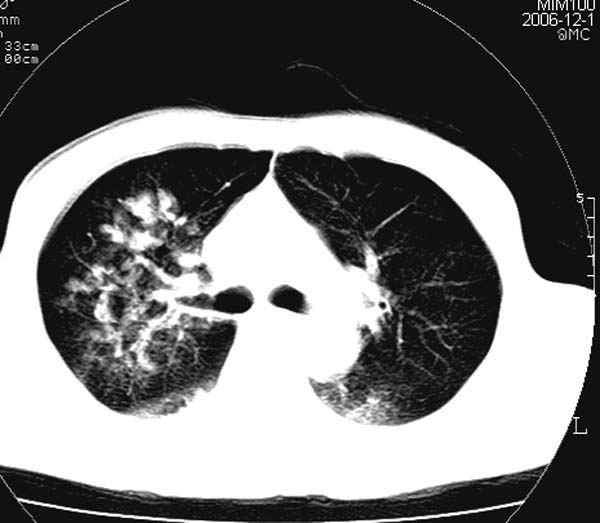

此病人是摔伤后12小时,38岁,无结核病史。谢谢

对不起各位,学着发图片,所以没有发全。此病人是摔伤后12小时,38岁,无结核病史。谢谢!

影像必须密切结合临床!此病例首先考虑肺撕裂伤,间质性改变为主,右侧有创伤性湿肺表现。鉴别诊断诸位大虾已经说得非常ok了。

结合病史,考虑肺挫伤可能,双侧少量胸腔积液.建议短期复查.

肺挫裂伤是肯定有。原来可能有结核或尘肺

影像必须密切结合临床!此病例首先考虑肺撕裂伤,间质性改变为主,右侧有创伤性湿肺表现。鉴别诊断诸位已经说了。

此病例首先考虑肺撕裂伤,间质性改变为主,右侧有创伤性湿肺表现,可短期治疗复查。